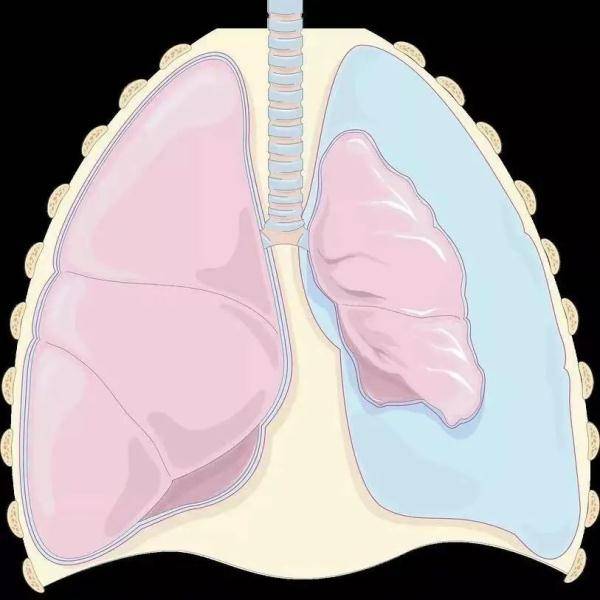

“俗话说的肺‘炸’了 , 其实就是医学上的自发性气胸 , 一般是因为非外力因素导致肺大泡破裂 , 使得肺里面的气体进入胸膜腔 , 出现胸闷、呼吸困难等不适症状 。 ”温医大附二院重症医学科副主任医师张晓隆介绍说 , 胸腔就像个封闭的盒子 , 而胸腔中左右两肺就像盒子中的两个气球 。 气胸就是肺像气球一样破了 , 胸腔内就会充气 , 严重时气胸会使人难以呼吸 , 甚至压迫大血管 , 或使心脏及血管移位 , 导致循环衰竭 , 有致命的风险 。

左肺压缩 , 蓝色的代表气体 。